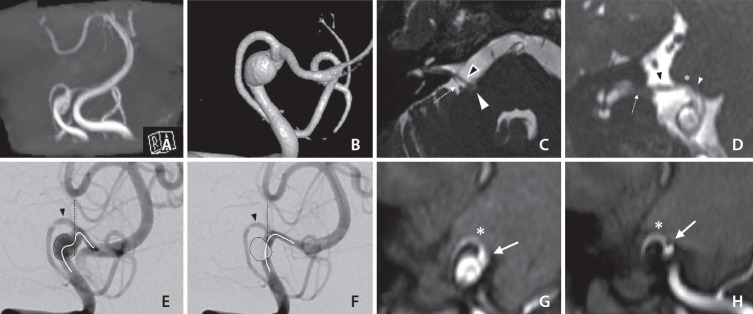

45岁女性,表现为进行性右半面肌痉挛(HFS)超过6个月。磁共振成像显示右侧小脑后下动脉(PICA)为HFS的罪魁祸首血管,其近端椎动脉(VA)有梭状动脉瘤。根据患者血管内治疗VA的要求,支架辅助线圈栓塞,通过支架置入后的VA矫直实现PICA偏差,从而减轻HFS症状。手术后21个月,患者的HFS得到解决,影像学证实异食癖偏离是由于VA矫直,这表明这种解剖改变有助于症状的解决。

A 45-year-old female presented with progressive right hemifacial spasm (HFS) over 6 months. Magnetic resonance imaging revealed the right posterior inferior cerebellar artery (PICA) as the culprit vessel for HFS and a fusiform aneurysm in the vertebral artery (VA) just proximal to it. Following the patient's request for endovascular treatment of the VA, stent-assisted coil embolization was performed to achieve PICA deviation through VA straightening after stent placement and thereby reduce HFS symptoms. At 21 months post-procedure, her HFS had resolved, with imaging confirming PICA deviation due to VA straightening, suggesting that this anatomical change contributed to symptom resolution.